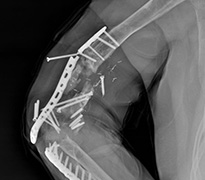

Yanlış Eğri Kaynama